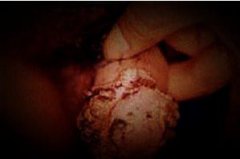

尖锐湿疣主要是患者的生殖器部位出现菜花状、鸡冠状、乳头状等形态的损害,不过一般的患者是不痒不痛的,对于尖锐湿疣建议患者最好是到正规的医院去及时的治愈,在尖锐湿疣的治疗上现在还是有很多种药物方法的,常见的就是手术、冷冻、激光等物理方法,这些方法是可以采用破坏性的物理手术帮助患者有效消除表面的症状,但是尖锐湿疣的病毒并没有全部都在疣体上,所以仅仅是消除症状还是不够的。